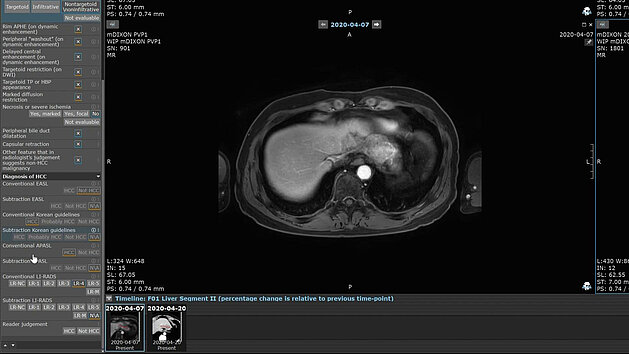

Postoperative Hirntumor-MRT mit Vergleich von TGSE-BLADE und RESOLVE DWI zur Darstellung von Artefakten und Resektionsareal

Eine aktuelle Studie im European Journal of Radiology vergleicht TGSE-BLADE DWI mit RESOLVE DWI in der postoperativen Hirntumor-Bildgebung. TGSE-BLADE zeigt signifikant weniger Verzerrungen und Artefakte durch intrakranielle Luft und ermöglicht eine präzisere Beurteilung ischämischer Veränderungen. Die Ergebnisse sprechen für TGSE-BLADE als robuste Alternative in der klinischen Routine.

Universitätsklinikum Tübingen: Verbesserung der postoperativen MRT bei Hirntumoren: TGSE-BLADE vs. RESOLVE DWI

Frühe MRT-Untersuchungen sind entscheidend für Patient:innen, die sich einer Hirntumorresektion unterzogen haben, um den Erfolg der Operation zu…